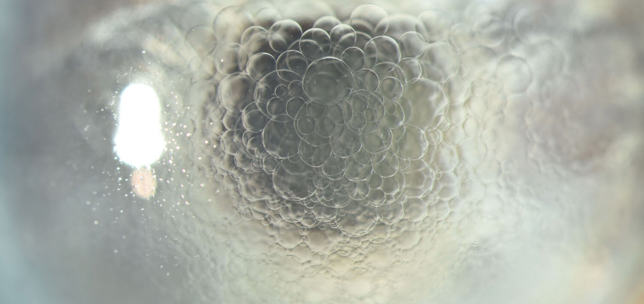

The ANTerior Segment Imaging Competition from Eye News and Keeler promotes and celebrates the work of slit-lamp imaging, culminating in cash prizes and exposure for its winners.

After a successful run in 2024, the ANTS Imaging Competition returned this year with another overwhelming response and our judges were thrilled to have so many amazing images to choose from. We would like to offer a huge congratulations to our winners, honorary mentions, and shortlisted entries, all of which can be seen below. So, without further ado, here some of the best ophthalmic imagers, optometrists and allied professionals in the UK right now: